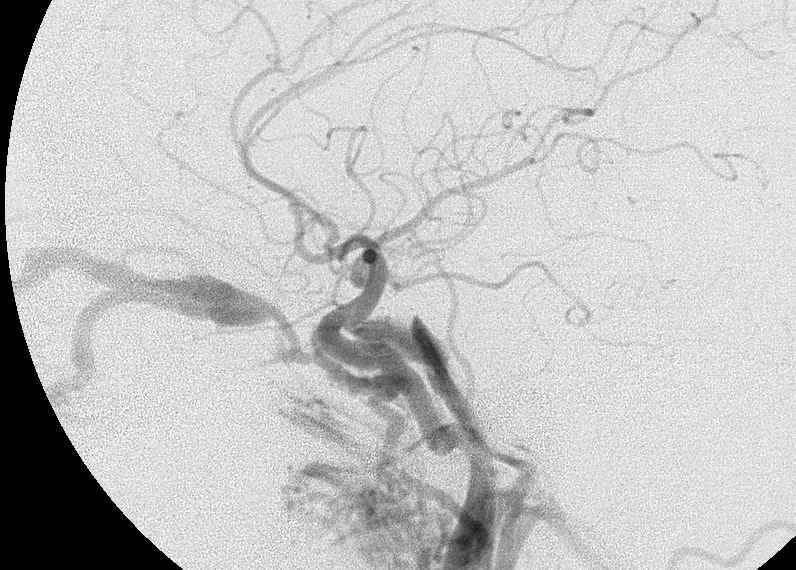

第一張影像為患者頭頸部非增強電腦斷層軸切面,可見左側眼球明顯前突(proptosis),伴隨左側 superior ophthalmic vein(SOV)擴張。眼眶內血管結構腫大及眼球向前推移符合高流量分流造成的靜脈回流受阻所致 SOV 擴張與眼眶組織充血(chemotic congestion)(ncbi.nlm.nih.gov)。第二張影像為數位減影血管攝影(DSA),可見頸內動脈海綿竇段(cavernous ICA)異常動靜脈連通,造影劑立即進入海綿竇及 SOV,顯示高流量、直接型 CCF 的典型徵象。